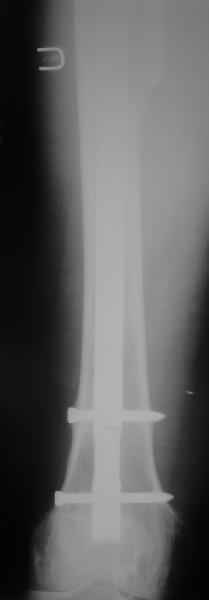

О качестве сращения перелома тоже сказать трудно. Выраженной мозоли нет. В боковой проекции отломки накладываются друг на друга. В прямой проекции зона перелома в наружной части закрылась не полностью. Возможно причина тому - недогрузка кости.

Обещанные ранее снимки Заранее спасибо.